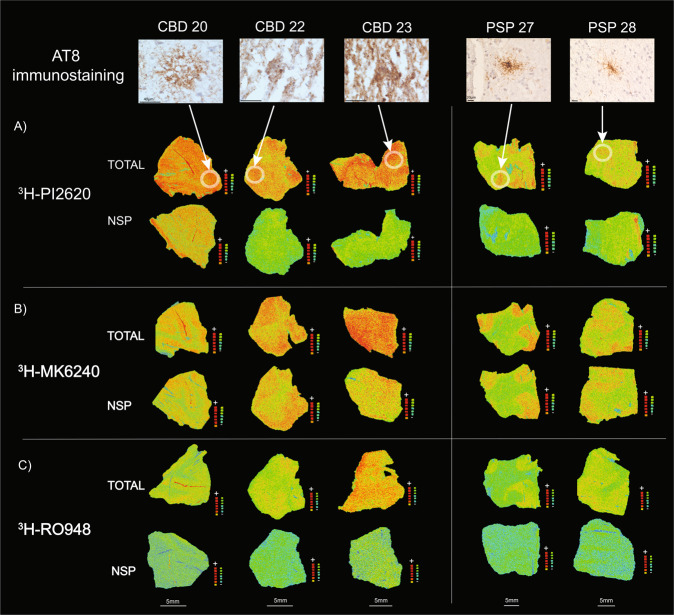

Small PSP and CBD section autoradiography

Autoradiography on small frozen FC sections (20 μm thick) from three CBD and two PSP cases, using 1 nM of 3H-PI2620, 3H-MK6240 or 3H-RO948, was carried out using the same protocol as above. The NSP binding was determined with 1μM of unlabelled PI2620, unlabelled MK6240 or unlabelled RO948, respectively.

Immunostaining on small frozen sections

Immunostaining was performed on adjacent frozen CBD and PSP brain sections, as used for the autoradiography studies. The sections were peroxidase-blocked for 5 min and protein-blocked using 5% non-fat dried milk powder at RT. The sections were exposed overnight at 4 °C to primary antibodies raised in mouse to target 3R + 4R tau (AT8; 1:1000 Cat.#MN1020, Invitrogen). Exposure to secondary antibody envision mouse HRP (Cat.#K4001 DAKO, Agilent Technologies) lasted 30 min at RT. The reaction was visualised by developing the sections in Peroxidase-blocking solution (Dako REAL). Between the different steps the sections were thoroughly washed in Tris Buffered Saline 1X + 0.05% Tween20 (TBST). Finally, the sections were dehydrated and mounted in cytosealXYL. All sections were treated simultaneously under the same conditions.

3H-PI2620, 3H-MK6240 and 3H-RO948 comparative autoradiography in CBD and PSP brains

The 3H-PI2620, 3H-MK6240 and 3H-RO948 autoradiography results from small frozen FC sections from the brains of three CBD and two PSP patients are shown in Fig. 6. Visual assessment of the results for the CBD and PSP tissue demonstrated that 3H-PI2620 binding was significantly more intense for total than for NSP binding. For 3H-RO948, some differences were observed between total and NSP binding but to a much lower extent than for 3H-PI2620. For 3H-MK6240, both total and NSP binding intensities were high in most cases. A quantitative evaluation of the binding properties of 3H-MK6240 and 3H-PI2620 was performed; total, NSP and specific binding values in fmol/mg are shown in Table 2. The percentage of specific binding for 3H-PI2620 (Fig. 6A) was very high in CBD samples (CBD 20: 58%, CBD 22: 77% and CBD 23: 71%). The percentage of specific binding for 3H-MK6240 (Fig. 6B) was lower (CBD 20: 24%, CBD 22: 0% and CBD 23:29%). The findings were similar in PSP tissue; there was a high percentage of specific binding for 3H-PI2620 (PSP 27: 73%, PSP 28: 44%) and a lower percentage of specific binding for 3H-MK6240 (PSP 27: 18%, PSP 28: 12%). The specific binding for 3H-PI2620 in the CBD samples ranged from 27.6 to 62.3 fmol/mg and 20.3 to 34.9 fmol/mg in PSP samples while, for 3H-MK6240, the specific binding was lower, ranging from 0 to 19.9 fmol/mg in CBD samples and from 4.6 to 6.5 fmol/mg in PSP samples.

Tau immunohistochemistry in CBD and PSP brains

AT8 staining results for each case are shown in Fig. 6. The specific positivity of the AT8 immunostaining confirmed the diagnosis of PSP and CBD, by visualisation of disease specific tau changes, tufted astrocytes and astrocytic plaques considered as the morphological hallmarks of PSP and CBD respectively.

High AT8 staining was observed in the FCs, predominantly throughout the cortex of the three CBD cases [ref. 20, ref. 22, ref. 23], with specific staining of astrocytic plaques (see Fig. 6; Supplementary Fig.1) and some neurones (data not shown). Moreover, we also observed numerous AT8 positive neuropil threads. The FCs from the two PSP brains [ref. 27, ref. 28] showed more AT8 specific binding in the cortex than in the white matter; and mostly located in astrocyte-like structures: tufted astrocytes (see Fig. 6; Supplementary Fig. 1).

The binding assays on brain homogenates were sensitive enough to provide important information regarding the binding characteristics (Bmax and Kd) of the tracers. However, we believe that the low binding could be the outcome of various experimental factors. (1) The process of preparing the brain homogenates may have caused tissue rupture as a result of sheer force and solvent exposure which, despite our taking countermeasures, could have affected the protein conformations and folds (please refer to Timasheff et al. for further clarification [ref. 57]), thereby affecting the accessibility of the tracer to the binding sites. (2). The amount of tissue used for these experiments was quite low (0.5 mg), despite having been decided on by rigorous protocol standardisation and test experiments. As we have seen in several of our previous studies, increasing the amount of tissue resulted in more NSP binding of the tracers. (3) There may also have been interference from other regions (low in target) that were part of the ROI. This aspect was beyond our control as the tissues were received from brain banks; however, we endeavoured to minimise this interference. In this way, autoradiography studies reflect the in vivo behaviour of a tracer with more accuracy as the tissue’s integrity (along with target accessibility) is preserved. The small frozen brain section autoradiography studies with 3H-PI2620, 3H-MK6240 and 3H-RO948 in FC tissue from CBD and PSP brains explicitly demonstrated this. In both CBD and PSP tissue, there was an evident difference in 3H-PI2620 binding intensity between the total and NSP binding sections which was complemented by quantitative analyses, in contrast to previous studies showing no binding in the FC of PSP patients [ref. 23]. The specific binding of 3H-PI2620 was in the range of 58-77 %, for the three CBD cases, and 44-73 % for the two PSP cases. For CBD and PSP, specific binding values were ~ 3.1- and 2.9-fold higher, respectively, than in brain homogenates (compare Fig. 1 and Table 2; Specific binding). On the adjacent CBD and PSP small frozen brain sections, autoradiography using 3H-MK6240 showed a small difference between the total and NSP binding. The specific binding of 3H-MK6240 was unequivocally lower than that of 3H-PI2620 (~ 17 % in CBD sections and ~ 15 % in PSP sections). For 3H-RO948, we observed a difference in intensity between the total and NSP binding; however, the strength of the binding was lower than that for 3H-PI2620. Moreover, in small frozen CBD brain sections, 3H-PI2620 bound in a diffuse manner, with no frontier between the cortical grey matter and the white matter. Small frozen brain section autoradiography findings were further supplemented by immunostaining studies performed on adjacent sections of CBD and PSP tissue with AT8 (targeting 3R + 4R isoforms). We observed high AT8 immunoreactivity with AT8 in the grey matter (numerous tau threads), glial cells and white matter. AT8 immunoreactivity was higher in the superficial cortical layers of CBD tissue and in the deeper cortical layers of PSP tissue. In a laminar pathology such as AD, neurons are anatomically positioned in different layers in the cortex, which explains the distinctive border between the grey and the white matter observed with the three tracers [ref. 58]. In CBD the important glial pathology is more spread explaining why the tracers binding is more diffuse in the grey and white matter. Interestingly, in PSP pathology, even if the glial pathology was highly present, no laminar pattern was observed, and the tracers showed a higher binding in the grey matter compared to white matter (to a lower extent for 3H-RO948).